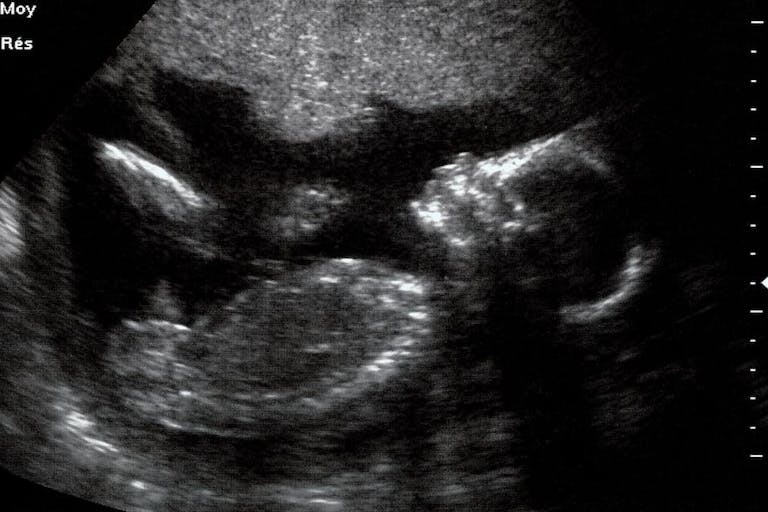

Shannon spoke with the States Newsroom about learning at 16 weeks by ultrasound that her preborn baby girl had Down syndrome along with a buildup of fluid in her head and body, a heart defect, and a tumor in her abdomen. The news outlet reported, “Each abnormality on its own would possibly have been manageable, Shannon said, but the maternal-fetal medicine specialist told her the combination meant she would likely either miscarry at some point during the pregnancy or her daughter’s life would be short and punctuated by multiple surgeries. Shannon and her husband made the difficult decision at that point to terminate.”

At 17 weeks, Shannon had an ultrasound to check for hydrops but it was not present. As the pregnancy progressed, the tumor grew .7 centimeters. These were not enough to deem her daughter’s health conditions ‘lethal.’